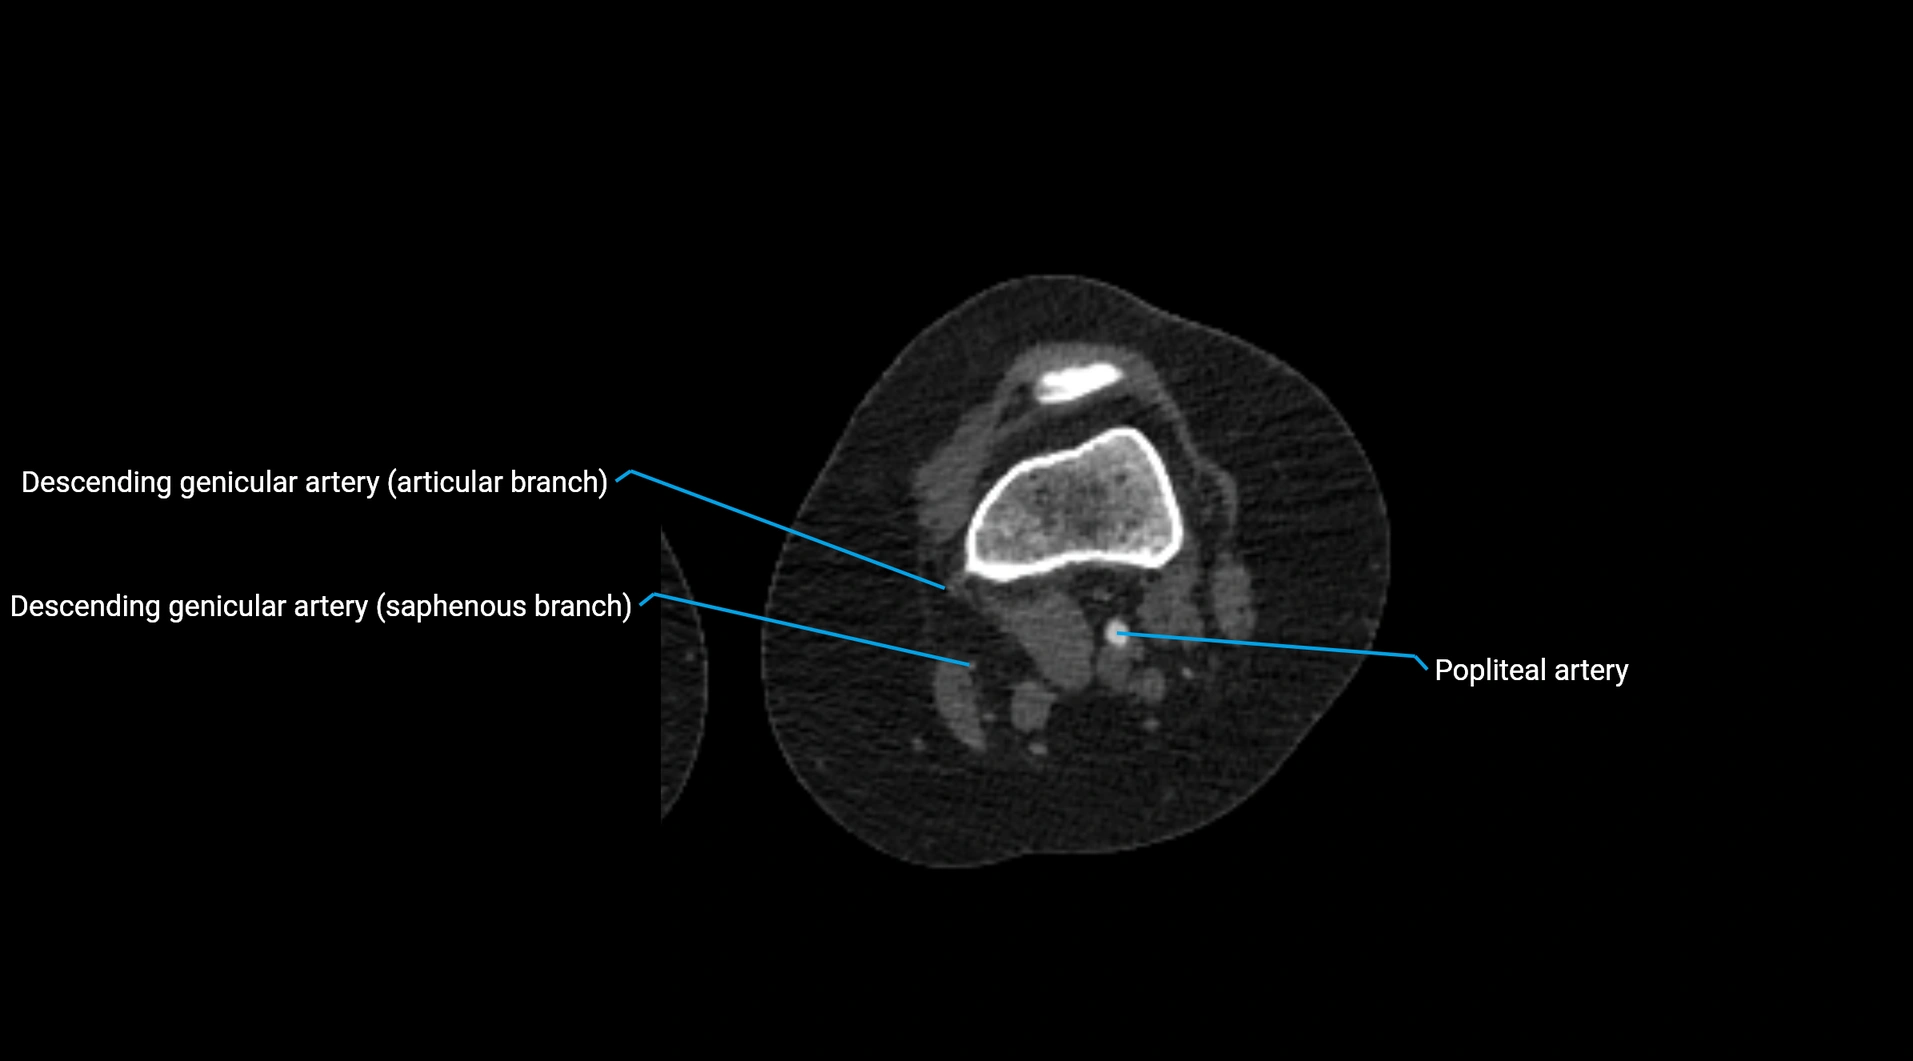

Contrast-enhanced CT (CTA):

• Gold standard for abdominal aortic imaging

• Provides excellent detail of lumen, wall, aneurysm, thrombus, and branch vessels

• Multiplanar and 3D reconstructions help in aneurysm measurement, stent graft planning, and dissection evaluation